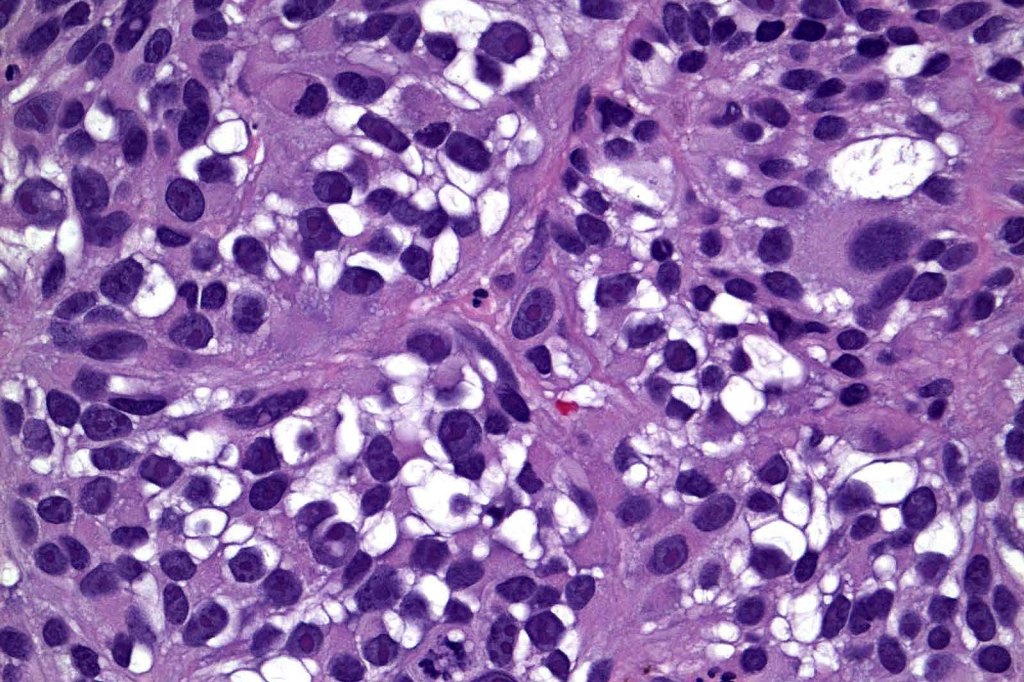

Clear cells may be intermingled with balloon cells in balloon cell melanoma. Only very exceptionally is a melanoma be composed of an almost pure cell population- clear cell melanoma. The clear cells differ from balloon cells in that they contain excessive amounts of glycogen which can be confirmed with a PAS stain. Clear cell melanoma must be distinguished from primary cutaneous or metastatic clear cell sarcoma and other clear cell tumors/carcinomas. Clear cell melanoma will likely show a junctional component in primary tumors, melanin pigment and positivity for S100 & HMB45. Clear cell sarcoma shows a characteristic t(12;22)(q13-14;q12 translocation, not present in melanoma.